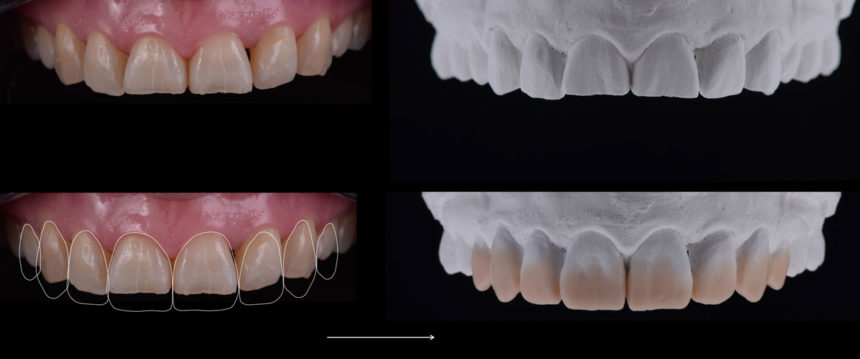

Εντατικό ολοήμερο πρόγραμμα πρακτικής εξάσκησης που έχει σχεδιαστεί για τη διδασκαλία των συμμετεχόντων οι οποίοι θα δημιουργήσουν άμεσες όψεις από σύνθετη ρητίνη που θα είναι ακριβώς όπως τα φυσικά δόντια.

Χρήση των κερωμάτων και των κλειδιών σιλικόνης για την καθοδήγηση της διαδικασίας αποκατάστασης.

Διαστρωμάτωση πολυχρωματικών αποκαταστάσεων σύνθετης ρητίνης και χρήση χρωστικών για τη δημιουργία εσωτερικών «εφέ».

Οι συμμετέχοντες θα ολοκληρώσουν άμεσες πρόσθιες όψεις (κυνόδοντας, πλάγιος και κεντρικός τομέας).

Το πρόγραμμα θα εστιάσει στα πρακτικά βήματα που χρειάζονται για την κλινική ολοκλήρωση αυτών των διαδικασιών.

- Ανάλυση των αποχρώσεων

- Χρήση των κερωμάτων και των κλειδιών σιλικόνης για την καθοδήγηση της διαδικασίας αποκατάστασης.

- Διαστρωμάτωση πολυχρωματικών αποκαταστάσεων σύνθετης ρητίνης και χρήση χρωστικών για τη δημιουργία εσωτερικών «εφέ».